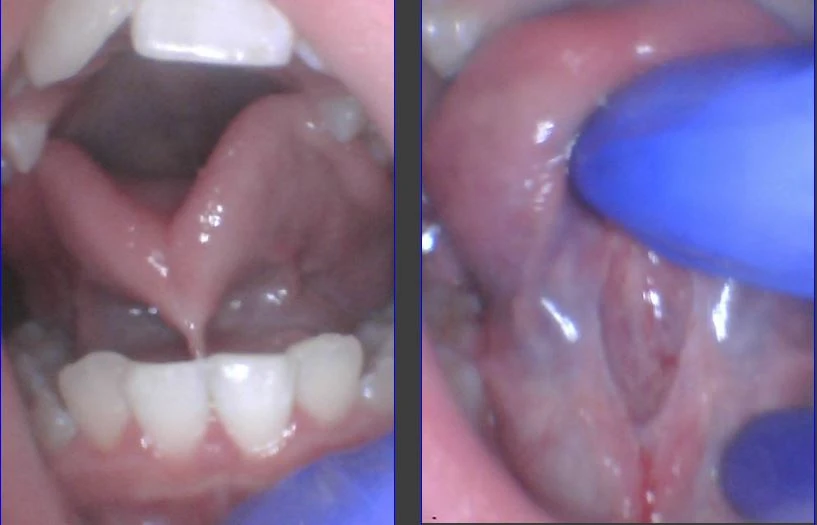

How Do You Check a Baby For a Lip-Tie and Tongue-Tie Properly?

Aug 25, 2020 | Tongue-Tie Tips

How to Check an Infant for a Lip-Tie and Tongue-Tie Properly Many dentists are asked to evaluate infants for a lip-tie or tongue-tie by concerned parents, but we were never trained in school how to do this. Although it’s too much to cover in one post, I’ll give you...